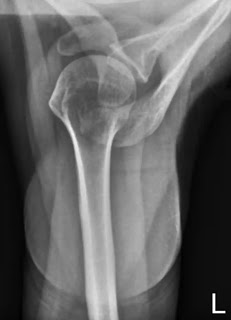

x ray for shoulder pain

1. Shoulder AP (15 degrees) erect

Direction and centring of the X-ray beam

Collimated horizontal x-ray beam के सेन्टर को scapula के coracoid process के ऊपर रखते हैं। central ray upper glenoid space से गुजरनी चाहिए जिससे कि humerus तथा acromion process separate(अलग) दिखाई दे।

Essential image characteristics

इमेज में humerus का head तथा proximal end, स्कैपुला का inferior angle तथा clavicle आदि शामिल होने चाहिए। इमेज Arrested respiration की स्थिति में होनी चाहिए।